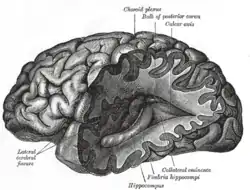

The pain signal travels from the periphery to the spinal cord along an A-delta or C fiber. Because the A-delta fiber is thicker than the C fiber, and is thinly sheathed in an electrically insulating material (myelin), it carries its signal faster (5–30 m/s) than the unmyelinated C fiber (0.5–2 m/s).[46] Pain evoked by the A-delta fibers is described as sharp and is felt first. This is followed by a duller pain, often described as burning, carried by the C fibers.[47] These A-delta and C fibers enter the spinal cord via Lissauer's tract and connect with spinal cord nerve fibers in the central gelatinous substance of the spinal cord. These spinal cord fibers then cross the cord via the anterior white commissure and ascend in the spinothalamic tract. Before reaching the brain, the spinothalamic tract splits into the lateral, neospinothalamic tract and the medial, paleospinothalamic tract. The neospinothalamic tract carries the fast, sharp A-delta signal to the ventral posterolateral nucleus of the thalamus. The paleospinothalamic tract carries the slow, dull, C-fiber pain signal. Some of these fibers peel off in the brain stem, connecting with the reticular formation or midbrain periaqueductal gray, and the remainder terminate in the intralaminar nuclei of the thalamus.[48]

Pain-related activity in the thalamus spreads to the insular cortex (thought to embody, among other things, the feeling that distinguishes pain from other homeostatic emotions such as itch and nausea) and anterior cingulate cortex (thought to embody, among other things, the affective/motivational element, the unpleasantness of pain),[49] and pain that is distinctly located also activates primary and secondary somatosensory cortex.[50]